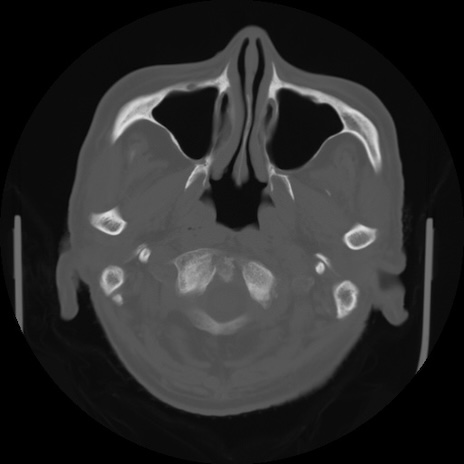

【頭部】症例5 CT(横断像)

【症例】80歳代 男性

【主訴】頭部打撲

【現病歴】外出先で椅子から立ち上がる際に、つまづいて後方へ転倒し受傷。転倒時に意識はあった。

【既往歴】高血圧、不整脈、アルツハイマー病

【身体所見】BP 217/71、HR 96、JCS1-1、 難聴あり、顔色良好、右後頭部に擦過創あり。神経学的異常なし。

症例5の画像所見と診断は?

CT(冠状断像)